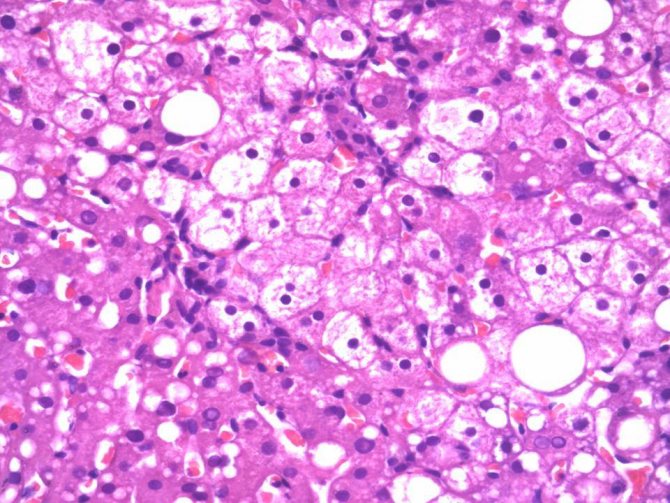

Схема морфологических изменений при холестазе